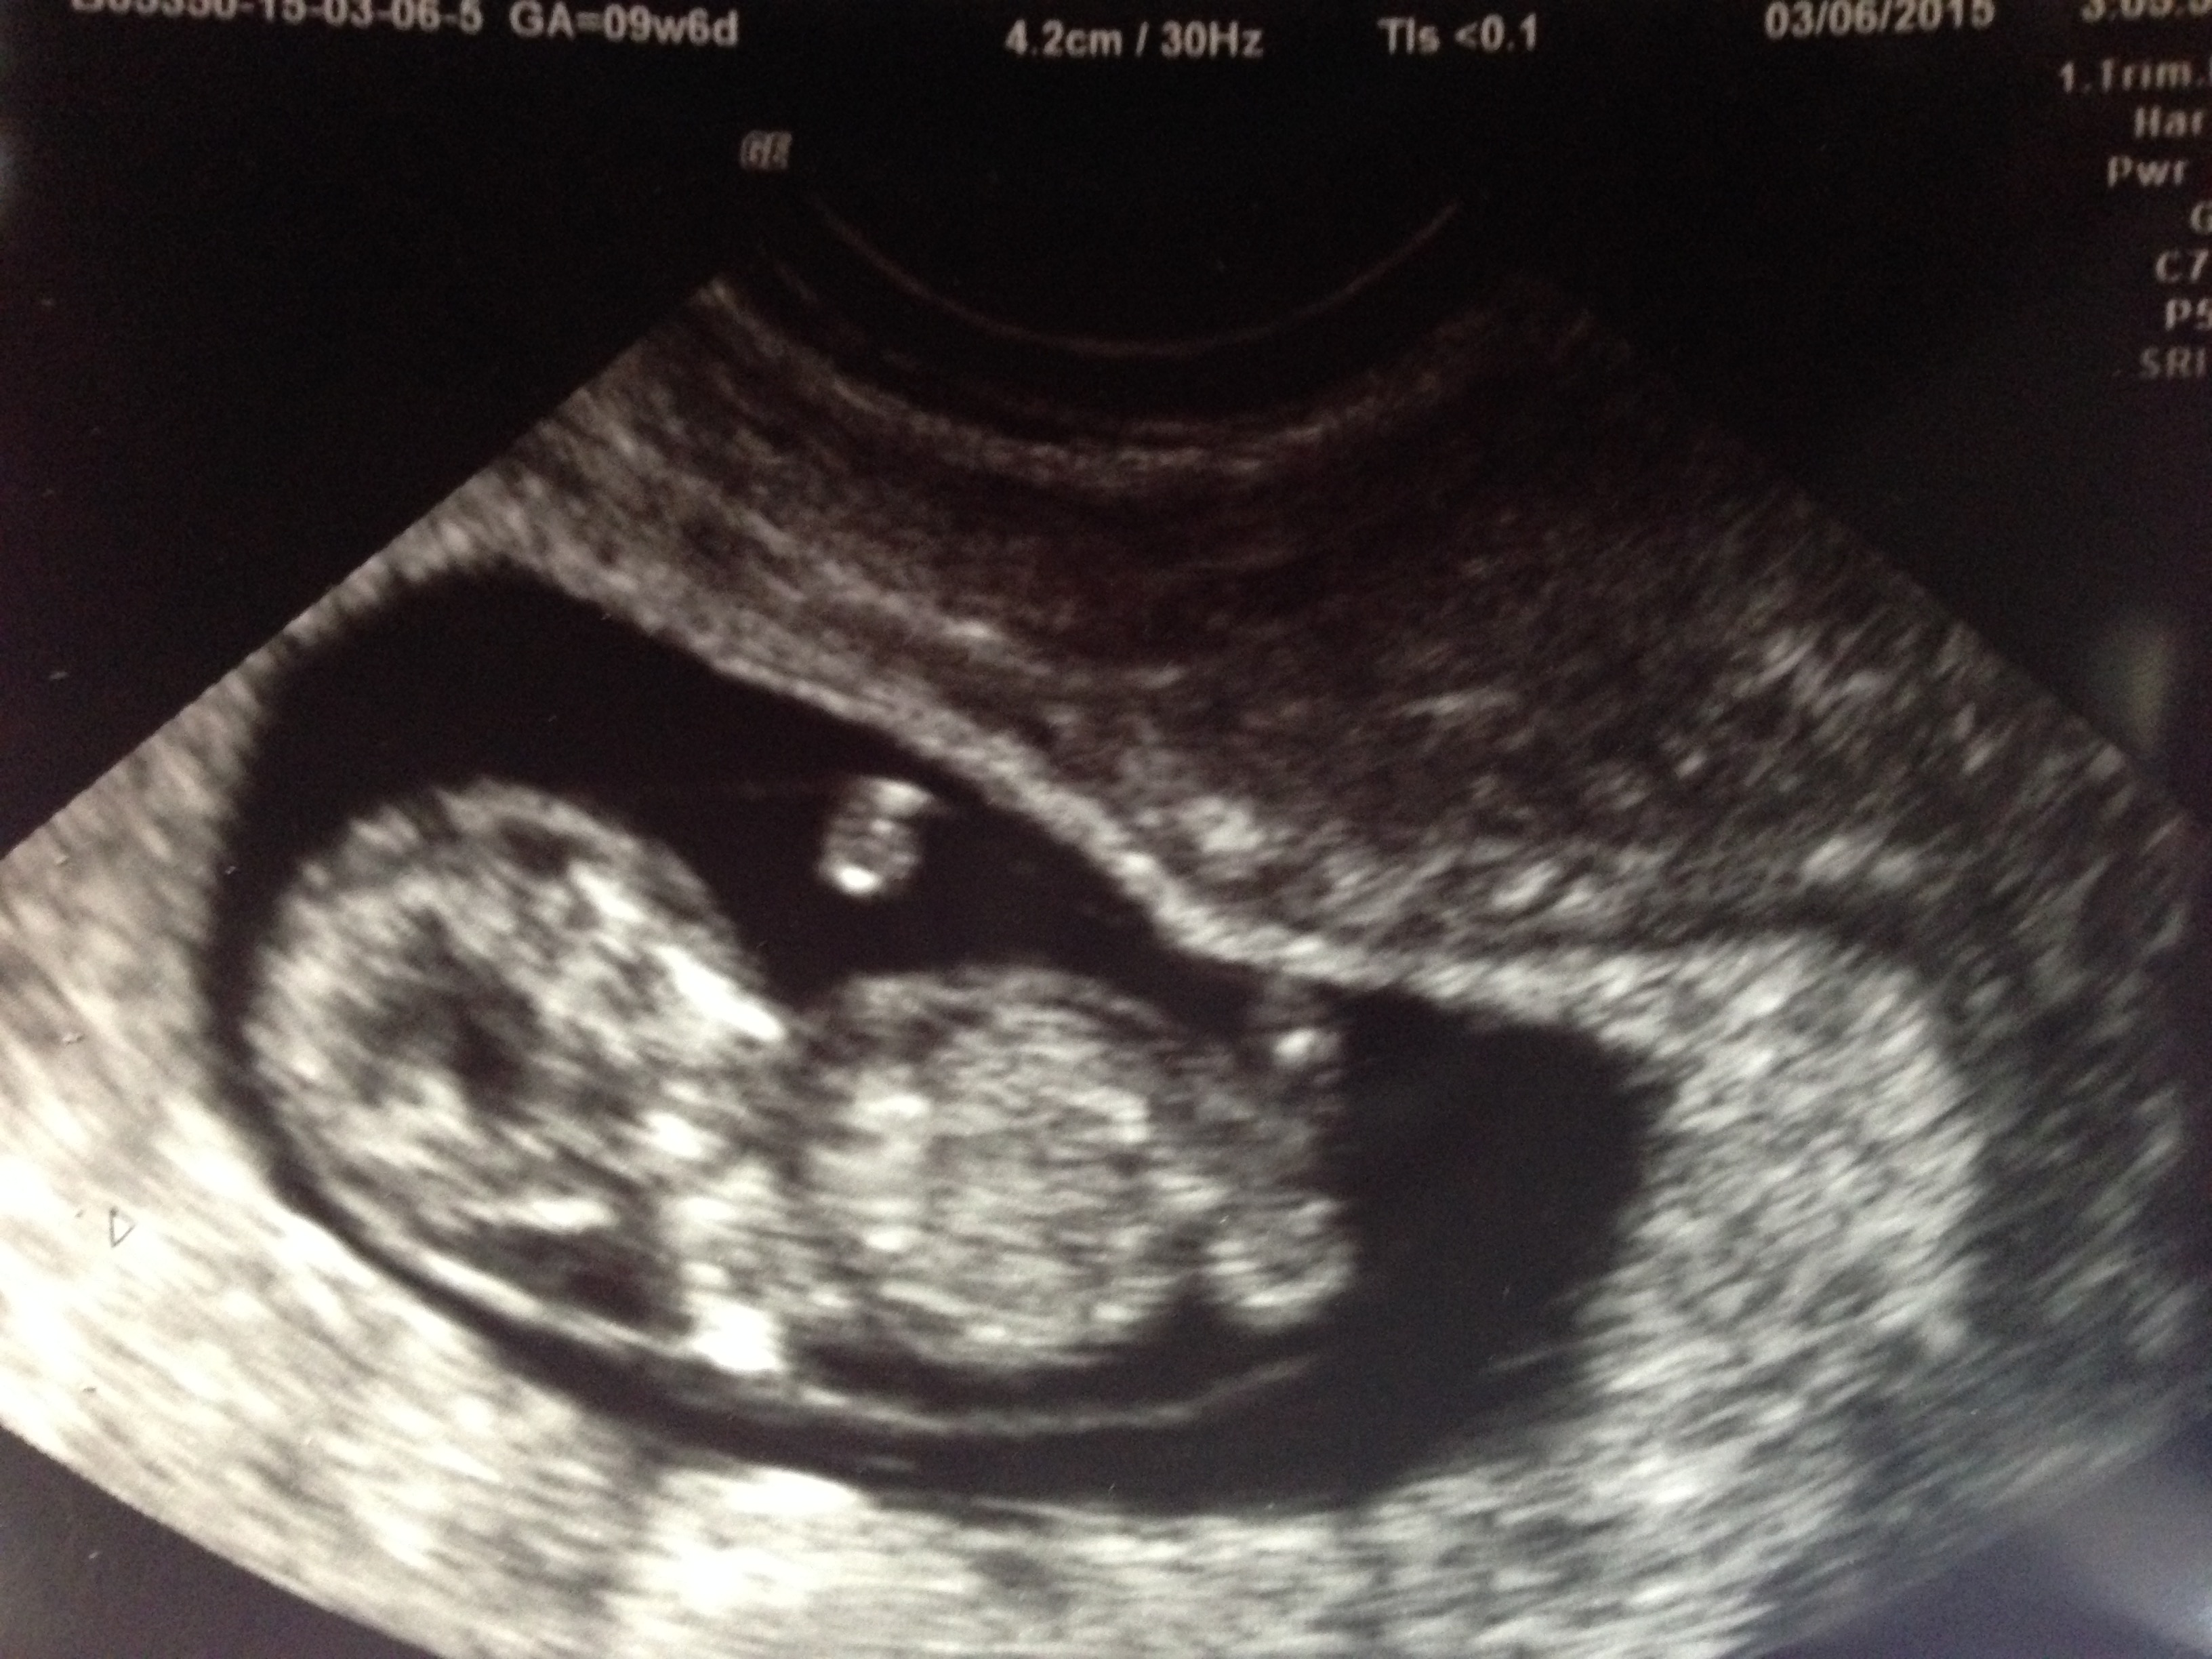

Baby Walton today (3/11) at 9w4d gestational age is +1 day! He even stretched his arm out during the U/S and we saw the heartbeat!! HR is 162 bpm so in love with this tiny thing!!